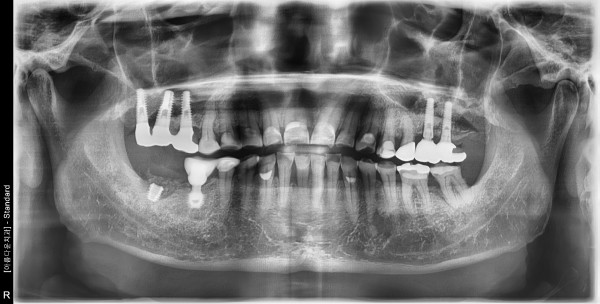

66세 남자 오른쪽 아래 어금니 (염증 심함)발치후뼈이식및 임플란트 식립